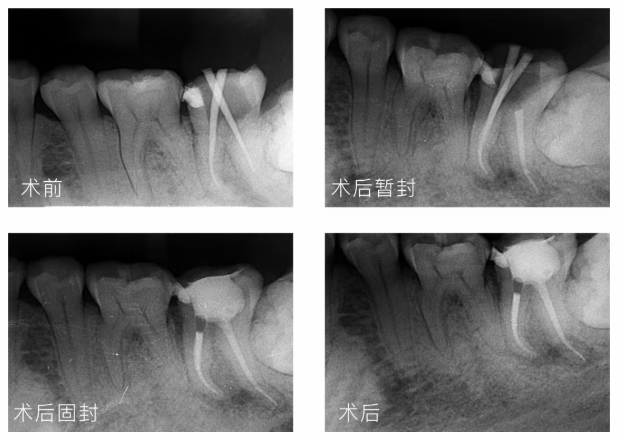

五、蓝晶灵根管治疗临床案例